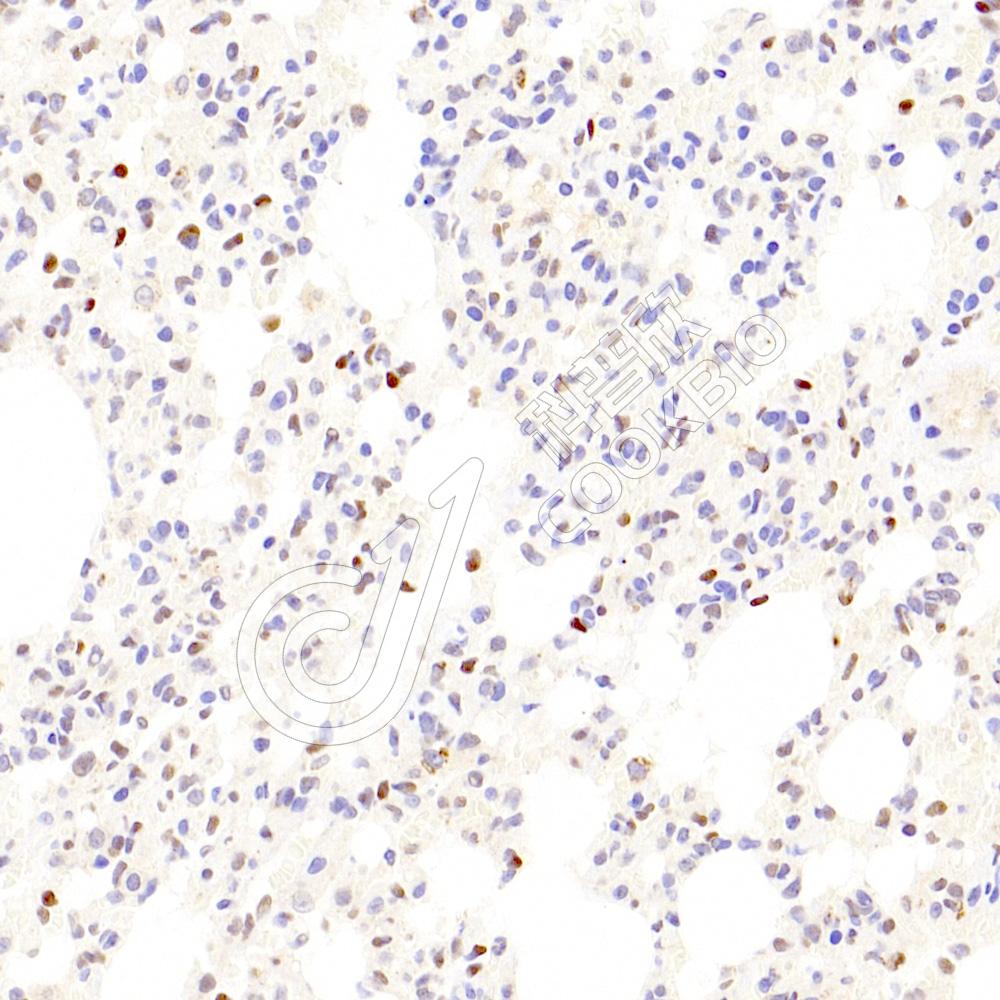

IHC检测ZEB1蛋白(货号 K134539).

样品: 大鼠肺, 4%多聚甲醛 (货号KSG1101) 固定12-24小时.

抗原修复: 柠檬酸抗原修复液(干粉, pH 6.0) (KSG1201), 98℃, 20分钟.

—抗: 1: 1000稀释, 4℃ 孵育过夜.

二抗: S-vision免疫组化多聚二抗(山羊抗兔),即用型 (货号KB3906), 室温孵育20分钟.